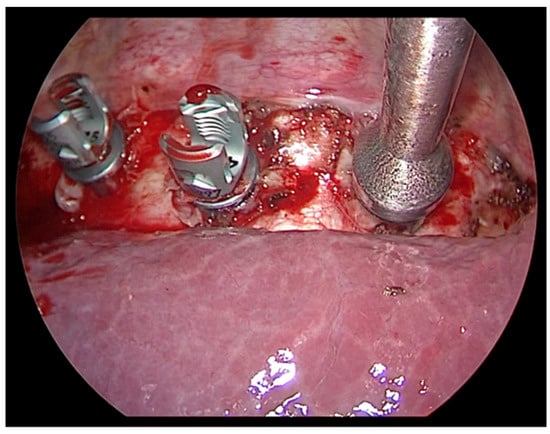

- Adequate trocars positioning is essential in order to correctly place the screws in the vertebral bodies. Fluoroscopy use in anterior and lateral view guides the orthopedist to the correct insertion.

- A correct interaction between pediatric and orthopedic surgeon, integrated by the combined use of thoracoscopic visualization and fluoroscopy, allow the orthopedist to correctly position the devices at the level of the vertebrae to be treated.